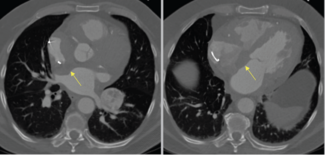

Charles Ritchie, MD; Nahyr S. Lugo-Fagundo, MD; Peter M. Pollak, MD; Jordan Ray, MD; Abdallah El Sabbagh, MD

An endobronchial alligator forceps was used to biopsy an RA mass under intracardiac echocardiographic guidance.